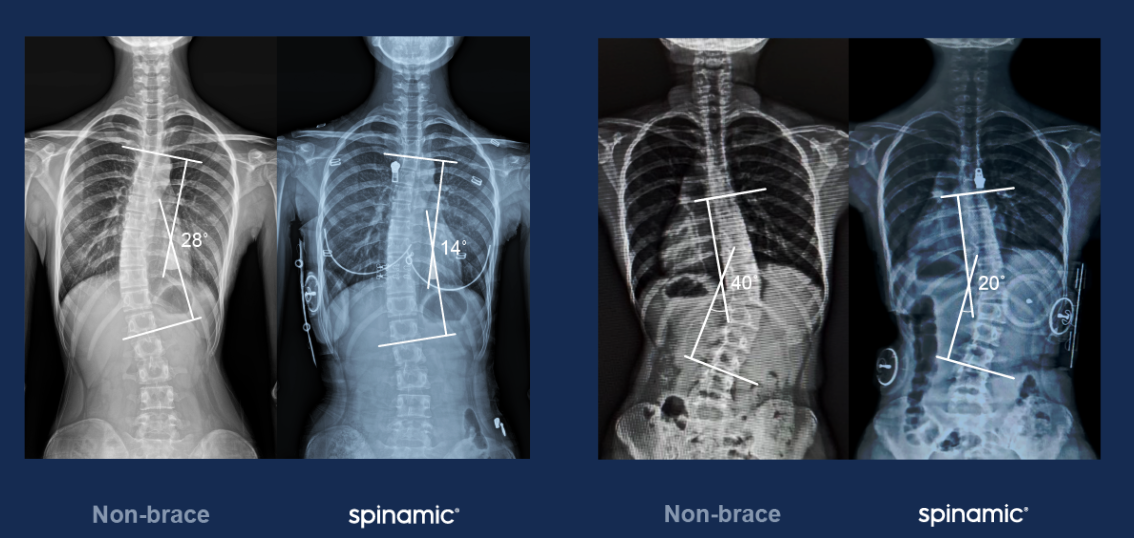

½ºÆÄÀ̳ª¹Í Âø¿ë ÀüÈÄ È¯ÀÚ X-ray ºñ±³

½ºÆÄÀ̳ª¹ÍÀº ÇöÀç 300¿©´ë ÀÌ»óÀÌ ÆÇ¸ÅµÆÀ¸¸ç Àüü ȯÀÚ¿¡¼­ ¸¸°î °¨¼Ò È¿°ú¸¦ È®ÀÎÇß´Ù.